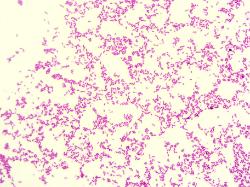

Pseudomonas aeruginosa, Gram stain.

Gram-negative, 0.5-0.8 x 1.5-3 μm rods, motile by a polar monotrichous flagellum

(exceptions may occur).